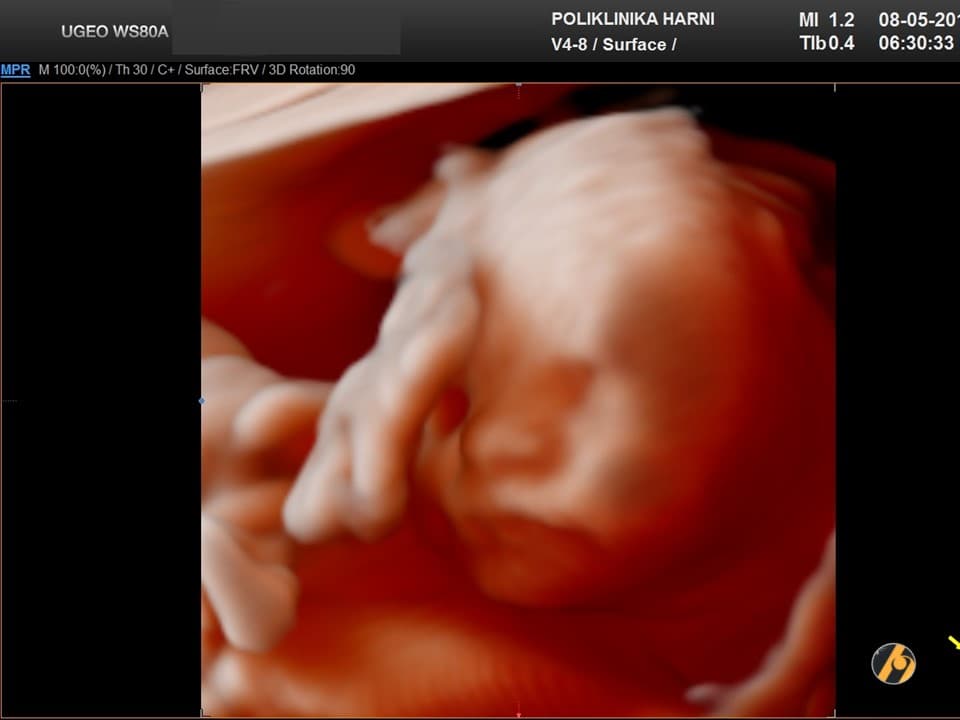

Fetus je dug približno 25 do 28 cm i težak oko 350 do 390 g. Razvijaju se okusni pupoljci, probavni sustav i krvne stanice.

U 21. tjednu trudnoće beba je duga približno 25 do 28 centimetara i teška oko 350 do 390 grama. Veličinom se često uspoređuje s većom bananom ili mrkvom.